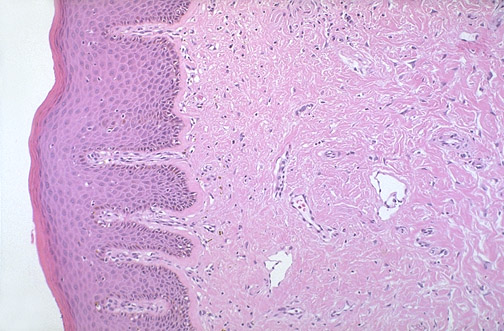

At medium power can be seen the overlying keratinizing

stratified squamous epithelium

of the epidermis. The dermis can be divided into the upper

papillary dermis

beneath the epidermis and the lower

reticular dermis

.